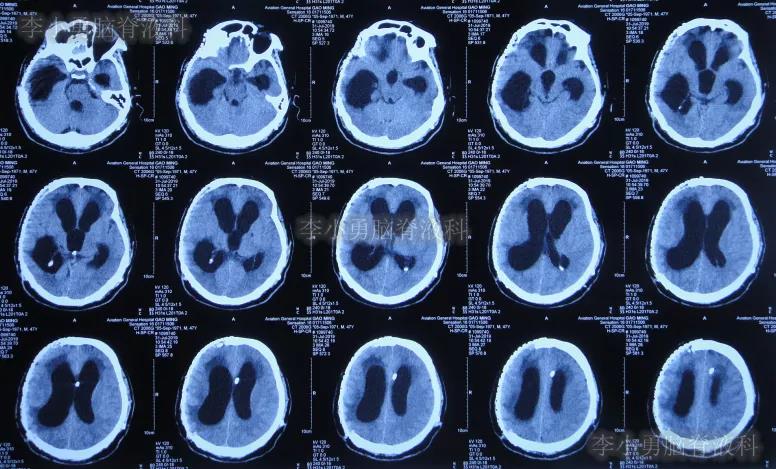

入院次日查头颅CT示颅骨修补术后,脑室引流后仍脑积水(图-9)。

图-9:2020年1月19日头颅CT

当天给予了拔除原脑室腹壁外引流管+脑室外引流术(图-10)。

图-10:2020年1月19日术后头颅CT

入院治疗24天即2020年2月11日,进行了脑室腹壁外引流术,术后当天查头颅CT(图-12)。

图-12:2020年2月11日头颅CT

入院治疗34天即2020年2月21日,查头颅CT示脑室进一步有缩小(图-13)。

图-13:2020年2月21日头颅CT